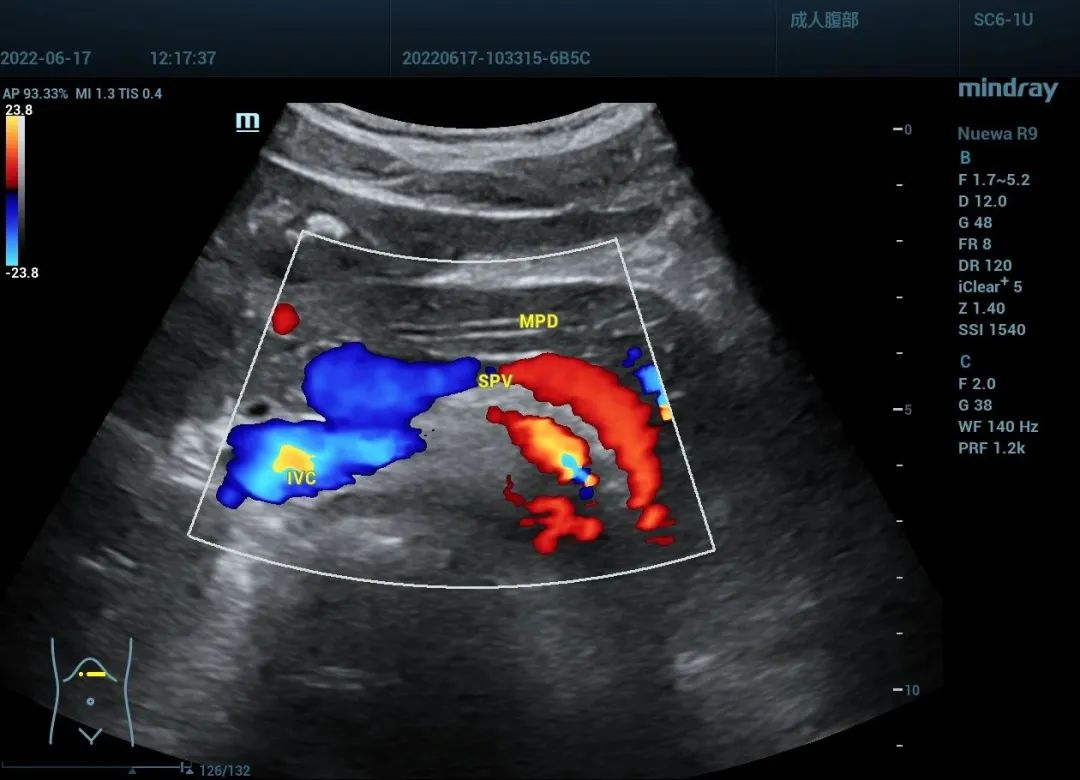

腹部血管:

门静脉高压征血管参数变化:

1.门静脉:主干内径<1.4cm,出现双向或离肝血流,血流期相性消失,平均流速降低(7.6±2.8cm/s);

2.肝动脉:代偿性扩张,内径0.4-1.0cm;

3.脾门静脉:内径>0.9cm;

4.附脐静脉:内径>0.3cm;

5.冠状静脉:内径>0.5cm。